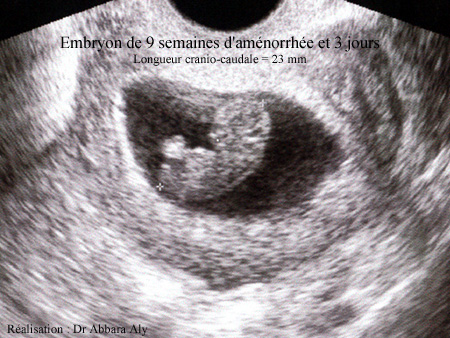

Grossesse de 9 semaines d'aménorrhée